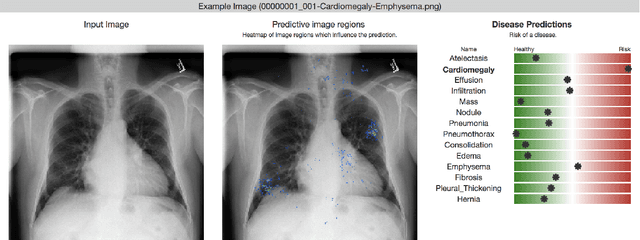

Abstract:Deep learning has shown promise to augment radiologists and improve the standard of care globally. Two main issues that complicate deploying these systems are patient privacy and scaling to the global population. To deploy a system at scale with minimal computational cost while preserving privacy we present a web delivered (but locally run) system for diagnosing chest X-Rays. Code is delivered via a URL to a web browser (including cell phones) but the patient data remains on the users machine and all processing occurs locally. The system is designed to be used as a reference where a user can process an image to confirm or aid in their diagnosis. The system contains three main components: out-of-distribution detection, disease prediction, and prediction explanation. The system open source and freely available here: https://mlmed.org/tools/xray/